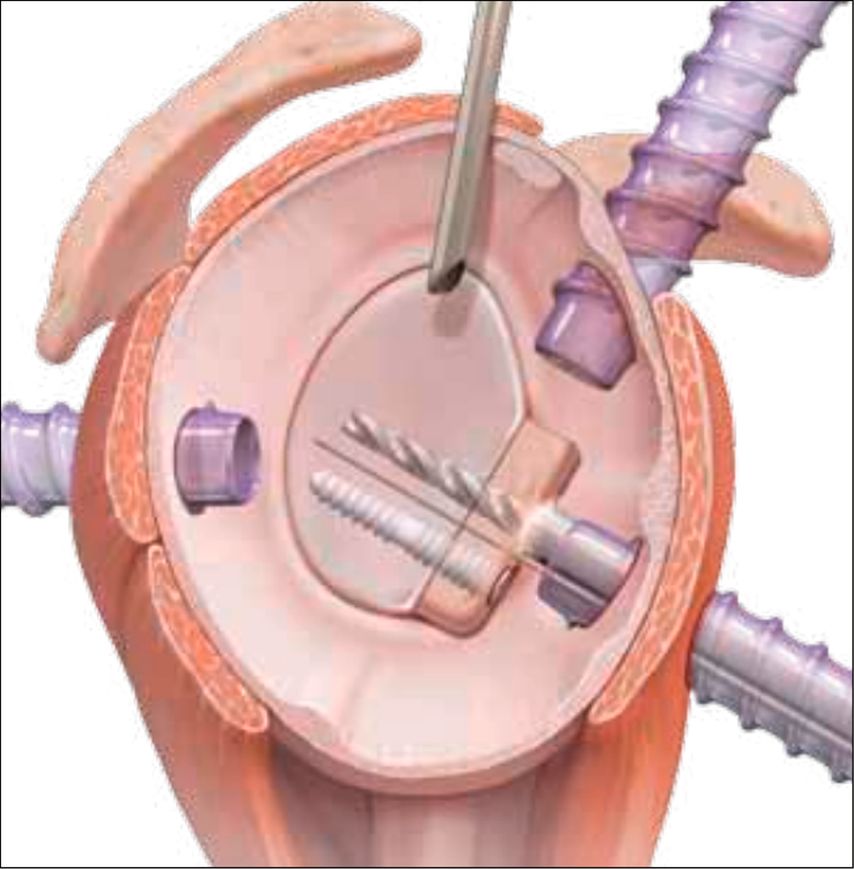

Der operative Eingriff wird in Beach-Chair- oder Seitenlagerung durchgeführt, wobei der betroffene Arm in einem Armhalter frei beweglich gelagert wird. Nach Etablierung der Standardportale – bestehend aus einem posterioren Portal zur Optik sowie anterior-inferioren und anterior-superioren Arbeitsportalen – erfolgt die arthroskopische Inspektion des Glenohumeralgelenks. Als Nächstes wird ein zusätzliches transsubskapuläres Portal (5-Uhr-Portal) angelegt (Abb.3). Die Frakturpräparation umfasst die Entfernung von Hämatom- und Interpositionsgewebe, die Mobilisation des Fragments sowie das Anfrischen der Frakturflächen zur Optimierung der knöchernen Heilung. Die Reposition erfolgt unter arthroskopischer Sicht mithilfe geeigneter Repositionsinstrumente, gegebenenfalls unterstützt durch temporäre Fixation mittels Kirschner-Draht (Abb.4).

Zur definitiven Fixation stehen unterschiedliche Techniken zur Verfügung. Die arthroskopisch assistierte Schraubenosteosynthese wird meistens durch das 5-Uhr-Portal durchgeführt. Kanülierte Schrauben (2,7–3,5mm) bieten, insbesondere bei größeren, kompakten Fragmenten, eine hohe Primärstabilität, ihr Einsatz ist jedoch technisch anspruchsvoll und mit dem Risiko einer intraartikulären Implantatprominenz verbunden. In den letzten Jahren sind aber Systeme mit bioresorbierbaren Implantaten hinzugekommen, die für die vordere Glenoidaugmentation entwickelt wurden (Abb. 5). Dieses System eignet sich auch perfekt für die Fixation des Glenoidfragments.